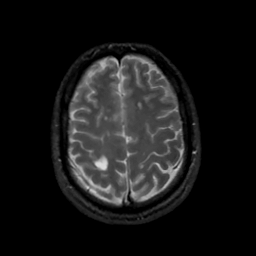

MR Study #13, May 19, 1991 -- Slice #39

[Home][Help][Clinical][Tour 1][Tour 2] Slice 39